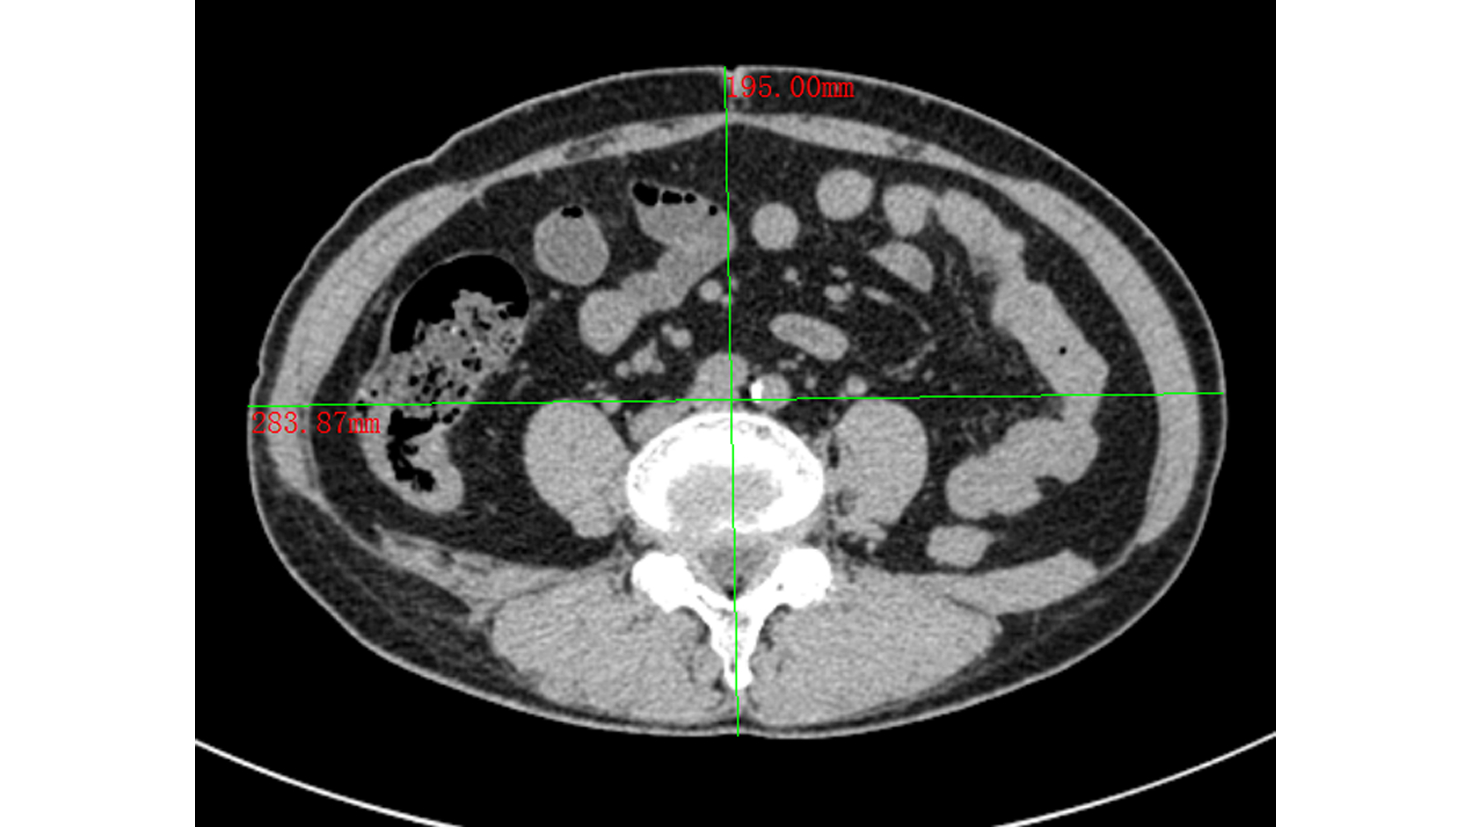

Establishment and application of a preoperative grading system for resectable pancreatic cancer

Chengfang WANG, Zhijiang WANG, Weilin WANG

2022, 38(10): 2325-2333. DOI: 10.3969/j.issn.1001-5256.2022.10.023

Abstract(945) HTML (545) PDF (2058KB)(65)

Abstract:

Objective  To investigate the risk factors for early recurrence of resectable pancreatic cancer and the establishment and application of a grading system.  Methods  A retrospective case-control study was conducted among 303 patients with resectable pancreatic cancer who underwent radical resection in Department of Hepatobiliary and Pancreatic Surgery, The Second Affiliated Hospital of Zhejiang University School of Medicine, from March 2015 to June 2021, and according to the presence or absence of early recurrence (within 6 months after surgery), the 283 patients directly operated on were divided into early recurrence group with 95 patients and non-early recurrence group with 188 patients; 20 patients who received neoadjuvant therapy before surgery were enrolled as neoadjuvant therapy group. Observation indicators included general information, preoperative imaging data, preoperative laboratory data, routine blood test/blood biochemistry and derived indicators, tumor markers, and coagulation markers, and follow-up was conducted to observe recurrence-free survival. The t-test was used for comparison of normally distributed continuous data between two groups, and the Mann-Whitney U test was used for comparison of non-normally distributed continuous data between two groups; the chi-square test was used for comparison of categorical data between two groups. A multivariate Logistic regression analysis was used to investigate the risk factors for early recurrence in patients with pancreatic cancer, and the receiver operating characteristic (ROC) curve was used to determine the optimal cut-off value of each indicator. The Kaplan-Meier curve was plotted, and the Log-rank test was used for comparison of recurrence-free survival time between groups.  Results  The univariate analysis showed that compared with the non-early recurrence group, the early recurrence group had significantly lower body mass index (BMI) and triglyceride and significantly higher CA19-9, CA242, CA125, and plasma fibrinogen (all P < 0.05). The multivariate logistic regression analysis showed that BMI (odds ratio [OR]=1.150, 95% confidence interval [CI]: 1.038-1.273, P=0.007), plasma fibrinogen (OR=2.513, 95%CI: 1.355-4.663, P=0.003), and CA242 (OR=2.482, 95%CI: 1.067-5.774, P=0.035) were independent risk factors for early recurrence in patients with resectable pancreatic cancer. BMI, CA242, and plasma fibrinogen were included in the grading system, with a cut-off value of 23.00 kg/m2, 30.0 U/mL, and 4.00 g/L, respectively. BMI < 23.00 kg/m2 was counted as 1 point, otherwise it was counted as 0 point; CA242≥30.00 U/mL was counted as 1 point, otherwise it was counted as 0 point; plasma fibrinogen ≥4.00 g/L was counted as 1 point, otherwise it was counted as 0 point; the total score was 0-3 points. The patients in both the early recurrence group and the non-early recurrence group were scored, and the results showed that the early recurrence group had a significantly higher score than the non-early recurrence group [2(0-3) points vs 1(0-3) point, Z=-5.339, P < 0.001]. The Kaplan-Meier curve analysis showed that there was a significant difference in time to recurrence between groups (χ2=28.116, P < 0.001), and the higher the score, the shorter the expected time to recurrence. The patients with 3 points were defined as high-risk group and those with 0-2 points were defined as low-risk group, and the early recurrence rate was 84.6% in the high-risk group and 31.2% in the low-risk group.  Conclusion  The grading system based on BMI, plasma fibrinogen, and CA242 can reliably predict postoperative recurrence.